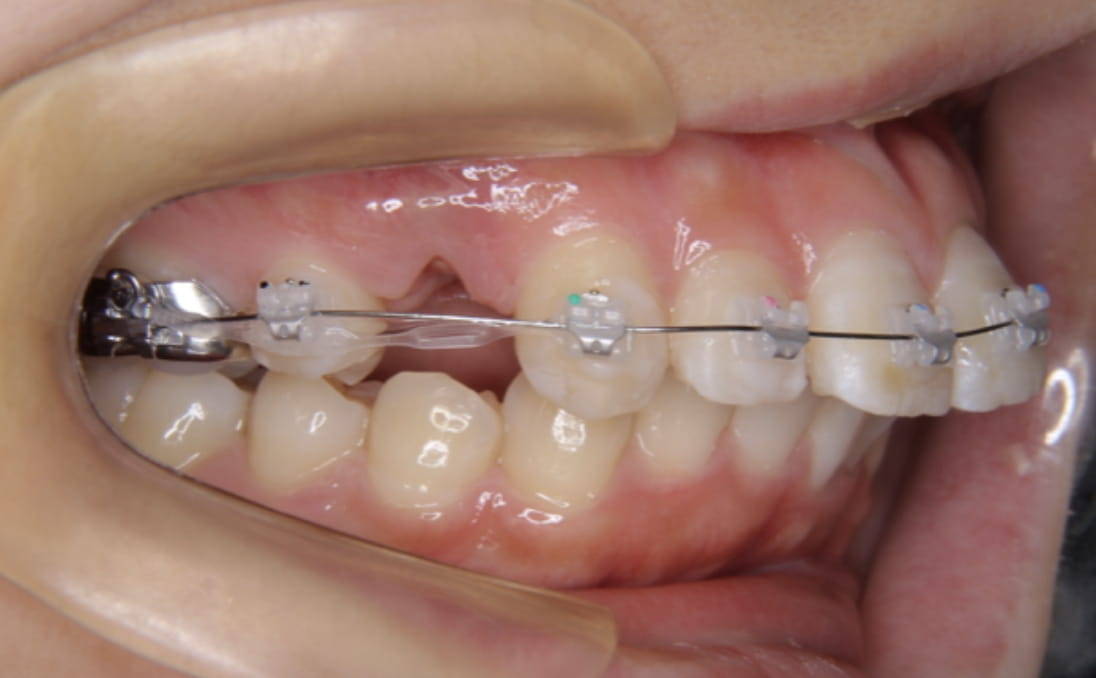

《上下顎前突》

症例

主訴 口ゴボが気になる

治療装置 ハーフリンガル矯正(上顎裏側・下顎表側)

抜歯 抜歯あり

診断名 上下顎前突(口ゴボ)

副作用 歯肉退縮・歯根吸収・歯髄・壊死・癒着による予期せぬ歯の動き

上下顎ともに裏側で装置を完全に隠しながら、アンカースクリューで前歯をしっかり後退。見た目と仕上がりを両立した症例。

治療前

治療中①

治療中②

治療中③